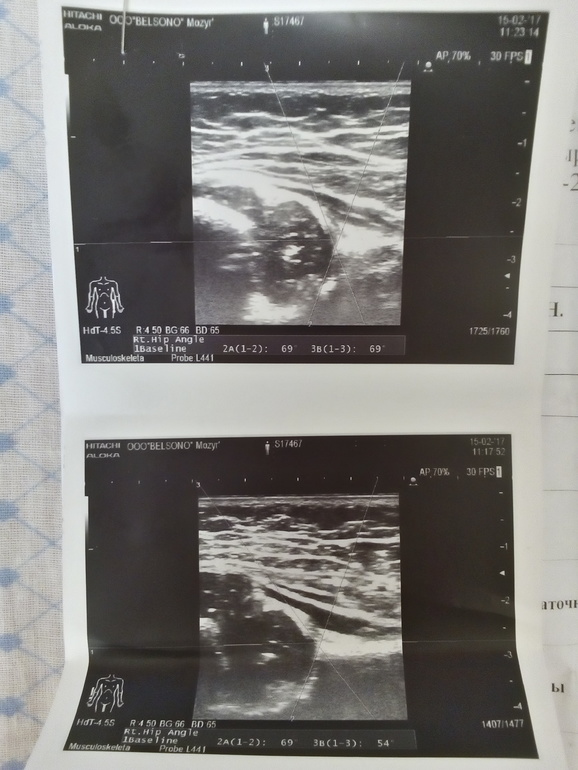

Меня беспокоят несемметричные складки у ребенка сделали УЗИ были у травматолога он исключил дисплазию,были у невролога врач посмотрел неврологических заболеваний тоже нет ножки разводит хорошо уже даже сесть хочет но ягодичные складки несемметричные я уже не знаю кому обращаться подскажите почему так??

Результат УЗИ